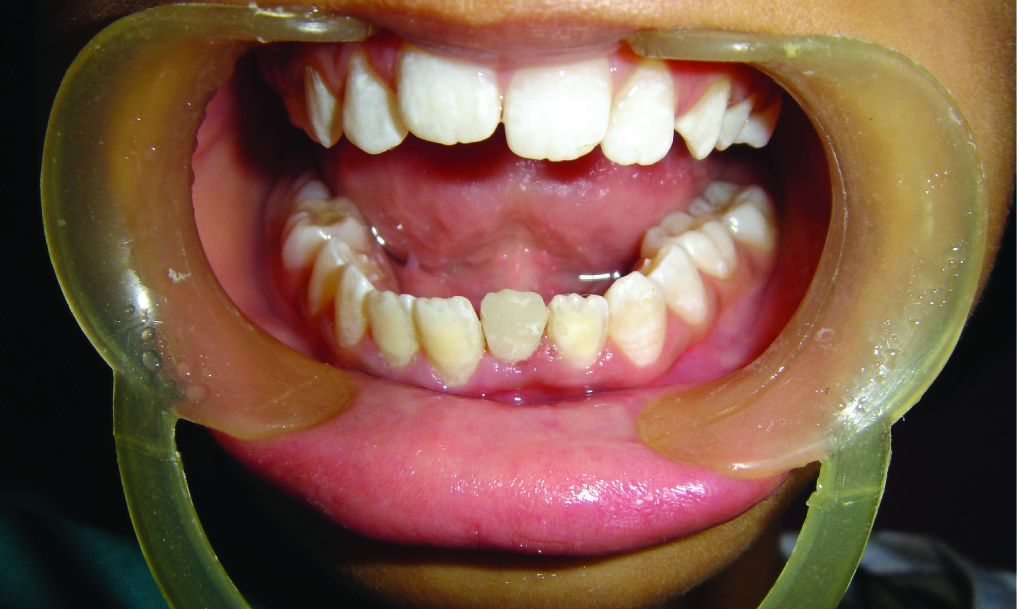

A 12-year-old female patient visited the Department of Pediatric Dentistry with a complain of broken left lower front tooth since four months. The patient did not complain of any pain [Table/Fig-1]. The parent of the patient told that the girl had a fall two years back in which the lower front tooth got broken. There was pain and tenderness reported at that time and they had visited a dentist for the same. On further enquiry it was revealed that the mentioned tooth had been root canal treated six months back and restored but the restoration came out within a month. The re-restoration also did not last more than 15 days. On examination lower left central incisor was fractured and there was neither pain reported nor tenderness to percussion. The tooth structure was less for a composite make-up or a crown. After thorough examination it was decided to go for a post and core and composite make up. As it was an anterior tooth in a young patient it was decided to go for fibre-reinforced composite (Ribbond, Ribbond THM, Ribbond inc.Seattle,WA) as post and core material as it is esthetic and has adequate strength. As the tooth was adequately obturated [Table/Fig-2], preparation of the canal space was done [Table/Fig-3,4]. The use of ribbond does not require additional tooth preparation as is required for metal posts. The remaining tooth structure being less, rubber dam isolation could not be accomplished and we decided for high suction evacuation with cotton rolls to be suitable for isolation. Gutta percha was removed using gutta percha solvent until the desired length for post was achieved. The post hole was shaped using Gates Glidden drills (Roydent, West Palm Beach, FL), cleaned with 5% sodium hypochlorite and dried. The width of Ribbond is to be decided on the root canal space available. The depth of the post space was measured using a periodontal probe, and a 3-mm-wide Ribbond was cut using special scissors provided with the kit (Ribbond starter kit, Ribbond THM, Seattle), measuring twice the depth of the post space and 3–4 times the height of the core build-up [Table/Fig-5] and placed in dual cure adhesive resin and set aside in light protected container. The root canal wall was etched, washed thoroughly and then air-dried gently. Excess water was removed from the post space using paper points . The dual cure adhesive resin (Ed Primer II A&B) was applied using a microbrush and gently air-dried to evaporate the solvent. Dual cure resin cement was then placed inside the canal space. The Ribbond was removed from the resin and the excess resin was removed using a hand instrument [Table/Fig-6], folded in a V-shape and coated with dual-curing resin cement (Panavia, Kuraray Medical Inc., Japan). The piece of ribbond was then placed in the post space in a labial-lingual direction with a periodontal probe [Table/Fig-7]. Excess resin cement was removed, and the cement was cured for 20 s. The two protruding ends of the Ribbond strips formed the reinforcement for the core build up to replace the lost coronal portion of the tooth. The remaining resin mix from the syringe was extruded onto this framework to create a core resembling almost like the shape of a lower central incisor. The space between the protruding ribbon ends was filled with resin so as not to leave any voids. Composite resin was also placed so as to cover the ribbon ends completely and leave none of them exposed on the outer surface of the core. All the material was thoroughly light cured to create a set surface. The material was left in the mouth for a couple of hours to ensure complete set of the self curing component of the resin mix. The result of this procedure came out to be a single piece post and core, which was bonded onto the root, creating a solid structure without any wedging effect on the root. Moreover, the resin conforming to the inside shape of the canal space ensured no voids and eliminated “fitting” problems normally associated with cast posts. The bands of Ribbond reinforced the resin material and made it extremely strong and durable. Bonding of the entire material also created a single block of post and core, which is the essence sought for favourable occlusal force transmission and for resistance against debonding of the entire unit. The best thing was, there was no metal to mask with the crown since the base shade of the composite was a close enough match to the tooth and was translucent. These strips, although opaque, were white in colour and after being completely encased in the composite, were not visible. However, they did not contribute to the colour of the core in any adverse way. The restorative procedure was completed by building up the tooth using dual cure hybrid composite resin following technique of small progressive build up without any matrix [Table/Fig-8,9]. All these increments were fully light cured. Finishing and polishing procedures were performed using composite contouring and polishing discs. The patient was advised for a crown at a later stage after complete development of occlusion. The patient has been under follow up for two years now with six month follow up intervals and the restoration is still in good condition [Table/Fig-10,11]. As because the occlusion is not yet established we have decided to give crown on a later date.